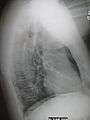

- Right lower lobe pneumonia as seen on a lateral CXR